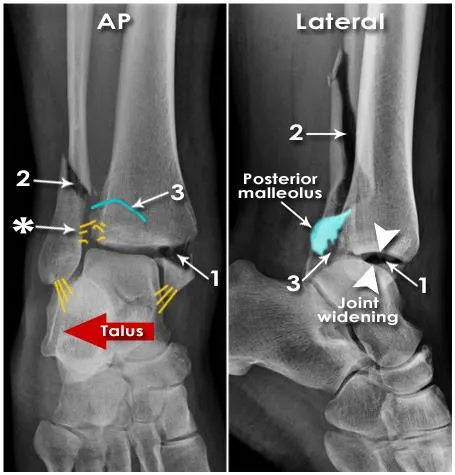

1.

Medial malleolus fx.

2.

Lateral malleolus fx. - proximal to the ankle and extending up the fibula (Weber C fx.)

3.

Posterior malleolus fx.

관절은 불안정하고 앞쪽으로 벌어짐 (화살촉)

distal tibiofibular syndesmosis 벌어짐 (* 표시)

Talus 가 뒤쪽, Lateral 로 전위되어 있음.

Unstable

Multiple ligamentous injuries

Usually involves syndesmosis

Treatment

Posterior slab

Urgent orthopedic consultation

ORIF